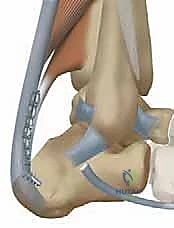

التشريح الحيوي: لماذا وتر (FHL) هو المنقذ المثالي؟

لفهم عبقرية هذه الجراحة، يجب أن نفهم التشريح. وتر العضلة المثنية الطويلة لإبهام القدم (Flexor Hallucis Longus - FHL) هو وتر يمر في الجزء الخلفي من الساق، قريباً جداً من وتر أخيل، ويمتد نزولاً ليتحكم في حركة انثناء إصبع القدم الكبير.

3. القرب التشريحي: يقع وتر FHL مباشرة بجوار وتر أخيل، مما يسهل عملية النقل الجراحي دون الحاجة لشقوق جراحية واسعة في أماكن بعيدة.

4. التروية الدموية: يتمتع وتر FHL بتروية دموية ممتازة، وعند نقله إلى وتر أخيل التالف، فإنه يجلب معه إمداداً دموياً جديداً يساعد في التئام الأنسجة المتضررة.

5. نقل وتثبيت الوتر (Tenodesis & Fixation)

هنا يتجلى الفن الجراحي. يتم حفر نفق صغير جداً في عظم الكعب (Calcaneus). يُسحب وتر FHL القوي ويُزرع داخل هذا النفق العظمي. يتم تثبيته باستخدام مسمار تداخلي حيوي (Bio-interference screw) يندمج مع العظم بمرور الوقت، مما يوفر تثبيتاً صخرياً قوياً.

بالإضافة إلى ذلك، يقوم الدكتور هطيف بخياطة ما تبقى من وتر FHL مع وتر أخيل الأصلي (Side-to-side anastomosis) لتعزيز القوة الميكانيكية المزدوجة.